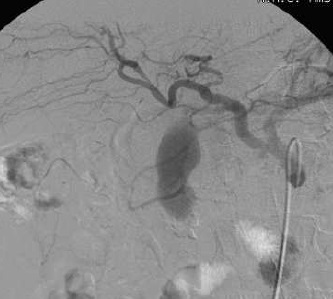

“ 弹簧栓子” 可供选择的Coil包括微弹簧栓子和0.035的普通弹簧栓子,释放弹簧栓子前需要用导丝检查导管的位置稳定的稳定性。第一个弹簧栓子的释放需要比血管的直径略大。假性动脉瘤或出血动脉的栓塞主要是栓塞载瘤动脉、或责任动脉,较少应用瘤囊填塞。有凝血障碍的时候,需要在Coil基础上使用液体胶等其它栓塞材料。结束栓塞取决于造影的结果。

经验性胃肠道出血的栓塞(Empiric GI embolisation) 仅根据经验和发现,而不是应用科学或理论的方法。所谓“Empiric” 所谓 包括病人的血氧饱和度、脉搏、血压以及负责检测的护士发现是指生理感官或延长生理感官的仪器的发现。所谓经验性胃肠道出血栓塞(Empiric GI bleeding embolization)是指血管造影并没有明确消化道出血来源根据临床判断对胃及十二指肠动脉进行栓塞,即所谓的“盲栓”(“blind” embolization) 让人想起电影《外星人》里的一句话:那就是为什么你失败了